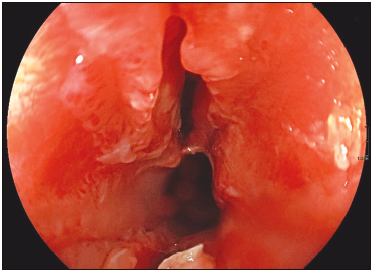

orofaringe sana, sin sobreagregados pulmonares, abdomen blando y sin signos de irritación peritoneal. La analítica de laboratorio muestra hemograma y electrolitos normales. Se realiza una radiografía toracoabdominal que evidencia aumento de la radiopacidad retrotraqueal en la proyección lateral del tórax, con posible compromiso inflamatorio esofágico y periesofágico, sin evidencia de cuerpo extraño. Con estos hallazgos se realiza una tomografía de tórax en la que se evidencia un engrosamiento concéntrico a nivel de esófago superior a 10 mm, sin evidencia de aparente perforación esofágica. Posteriormente, se realiza una endoscopía digestiva alta bajo anestesia, con evidencia de un cuerpo extraño de material plástico de 10 mm localizado a 15 cm de la arcada dentaria en el esófago proximal, incrustado en la mucosa sobre la pared esofágica. Posterior a la extracción con pinza de cuerpo extraño (Figura 1), se evidencia laceración profunda de la pared esofágica de 20 mm de longitud, sin descartar microperforación. (Figura 2).

Figura 2. Laceración profunda en esófago superior